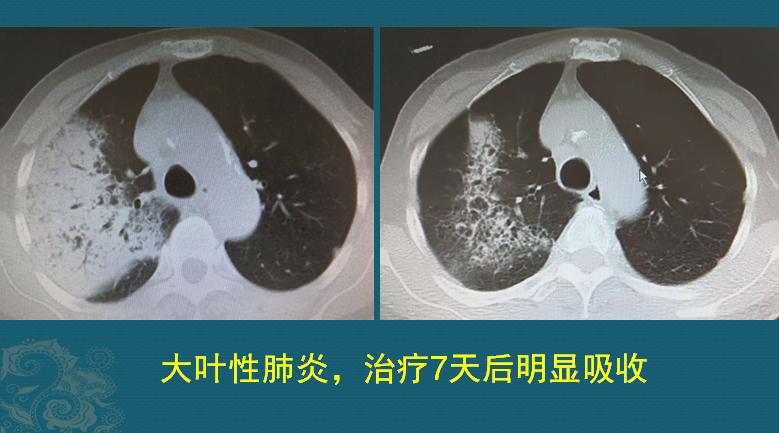

如果没有及时服用敏感抗生素,硬抗几天后,仍旧反复发热、咳嗽加重,这个时候再看医生,就可以用听诊器听到肺部异常声音,做个CT就会呈现下图这个样子:

右肺上叶大片高密度影,边界不清晰,里面可以看到光滑的支气管,这是典型的大叶性肺炎。白色高密度影是肺泡内大量纤维蛋白渗出液,之后伴随红细胞和白细胞的渗出等,发生肺组织实变(支气管仍然通畅、含气,像黑色小树枝样)。一般只局限于一个肺段或者肺叶,及时治疗可以完全吸收。

上图是一位70岁老爷子,发热、咳嗽、少量咳痰,在家里拖了10天才过来,右侧大叶性肺炎,抗生素治疗7天后明显吸收好转。